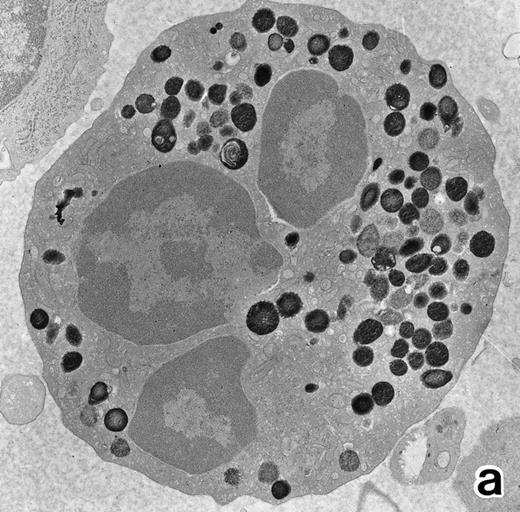

(a) A PMN that emerged in the APL cell culture of patient no. 3 in the presence of ATRA for 1 week. From the lobulated nuclear configurations and condensed heterochromatin, this cell looks like a PMN. However, the cytoplasm contains many MPO-positive primary granules but no secondary granules. (MPO-stained section, original magnification × 14,900.) (b) Higher magnification of a portion of the cell in (a), showing that the cytoplasmic granules are all MPO-positive. (MPO-stained section, original magnification × 30,100.)

APL cells in culture.APL cells in patient no. 3 were cultured in the presence of ATRA or G-CSF for 7 days, and their morphological changes were examined under a light microscope. After 5 days of culture with ATRA the cells displayed a tendency toward maturation, including nuclear lobulation, chromatin condensation, and a decrease or disappearance of azurophil granules, similar to that observed in bone marrow cells. The cells cultured with G-CSF for 7 days, on the other hand, retained a promyelocytic appearance with numerous azurophil granules that even seemed to have increased in size and/or number (data not shown). Electron microscopic examination showed the nuclei of the cells cultured with ATRA to be irregularly lobulated with marginally condensed heterochromatin and the lobulated nuclei to be often connected by nuclear filamentous structures, in a manner similar to the cells seen in the bone marrow (Fig 8). These cells contained numerous MPO-positive primary granules, including irregularly shaped granules, but no MPO-negative specific granules were identified.